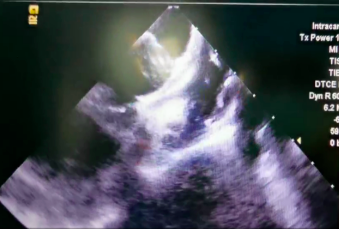

术后 ICE 评估左心耳有效封堵